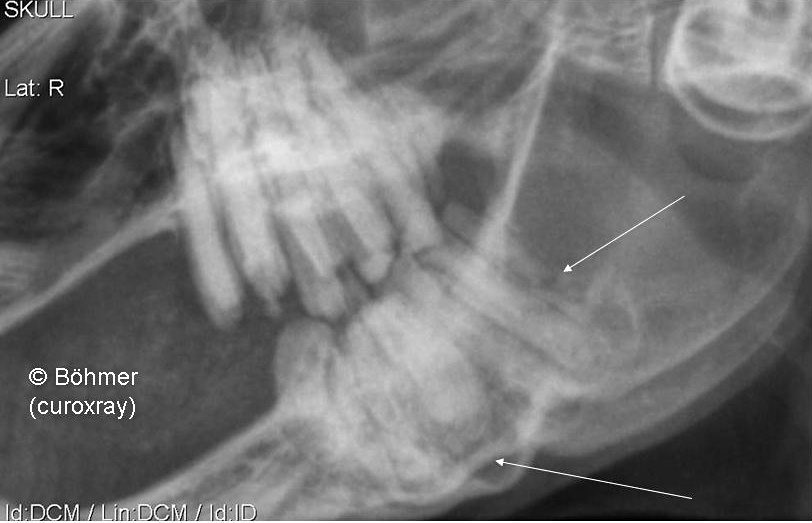

Radiography of

a rabbit with a mandibular jaw abscess

On the

radiography, it is possible to see: -

a fracture from side to side  and in the length of the last mandibular

cheek teeth (Side ? – an oblique view is needed in order to determine on whch

side the this tooth is located). -

Parodontopathia apicalis of the second mandibular cheek tooth (Side ? – an oblique

view is needed in order to determine on whch side the this tooth is located). -

Enamel and dentis hypoplasia of all maxillar and mandibular

cheek teeth.